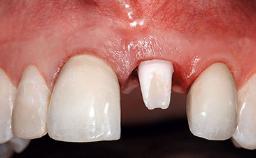

Replacement of a Compromised Upper Right Central Incisor: Hard- and Soft-tissue Augmentation, Late Placement of an RC Bone Level Implant

A 36-year-old male patient with a compromised maxillary central incisor was referred by his general dentist for consultation. The patient’s chief complaints were the gradual debonding of a temporary crown on the right central incisor and unsatisfactory esthetics due to an increasing diastema between the right central and lateral incisors. The patient reported a traumatic event some years previously, when a crown had been placed after root-canal treatment. The referring dentist wanted to provide a new crown restoration, but was concerned about the condition of the residual root. Anamnesis was negative for any other dental or periodontal pathology in the remaining dentition. The patient reported taking no medications: He was a smoker (10 to 15 cigs/day) and had realistic esthetic expectations.

Soft Tissue Anatomy Intact Defective

Soft Tissue Contour and Volume Slightly compromised